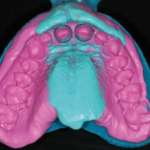

Viene documentato un case report, progettato e finalizzato attraverso un workflow digitale, per la realizzazione di una protesi superiore a supporto implantare e a carico immediato entro le 48 ore successive alla chirurgia